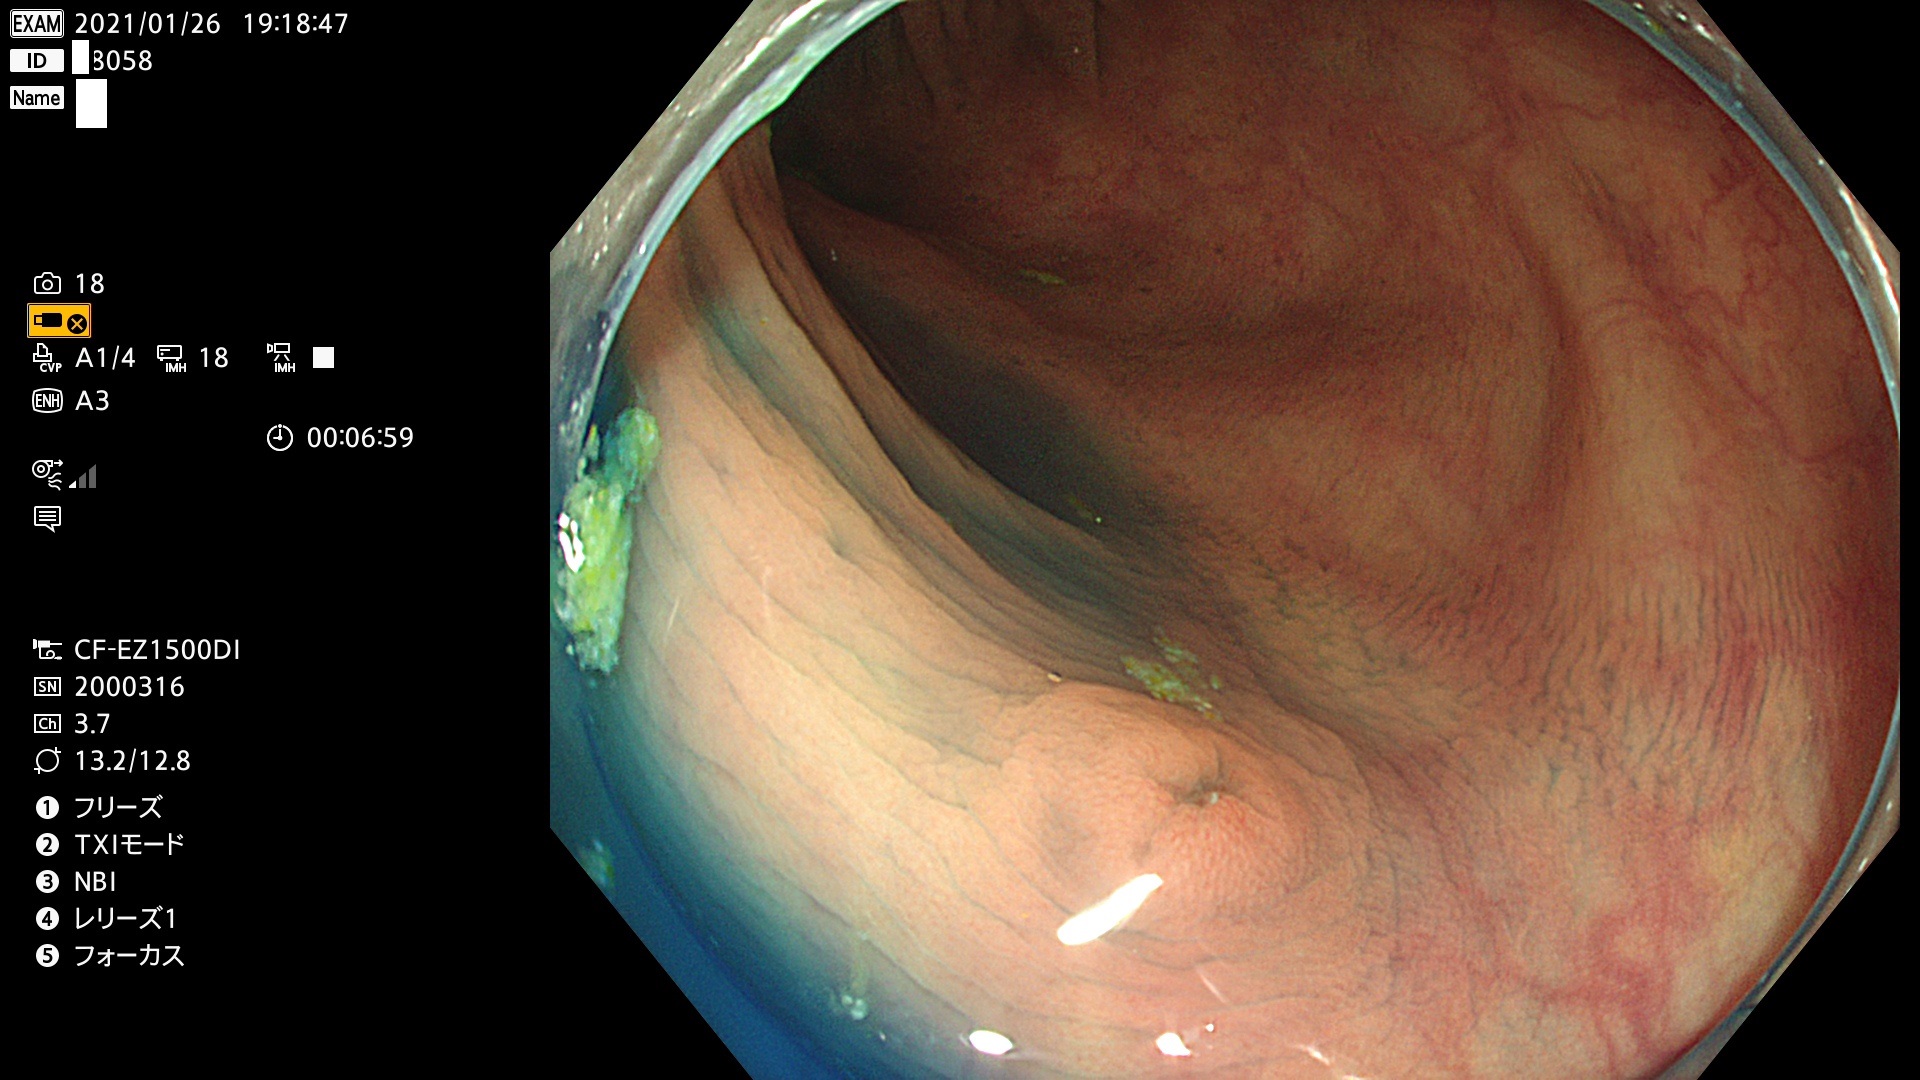

ビランと紛らわしいUc型腺腫(最も危険な前癌病変)

以下は当院で経験した「ビランと鑑別の難しいUc型腺腫」です(全て、病理で腺腫を確認済み)。

このような病変は表面を拡大観察しても診断は不可能であり、現在の内視鏡診断の「限界を超えた病変」と言えます。現実的な対策は「典型的なビランと異なる」と感じたら、「コールド法で積極的に切除する」ことと考えます。もちろん「結局はビランだった(不要な過剰切除だった)」ということもあります。しかしコールド法なら重篤な合併症は稀であり、医師は切除を躊躇すべきではないと考えます。